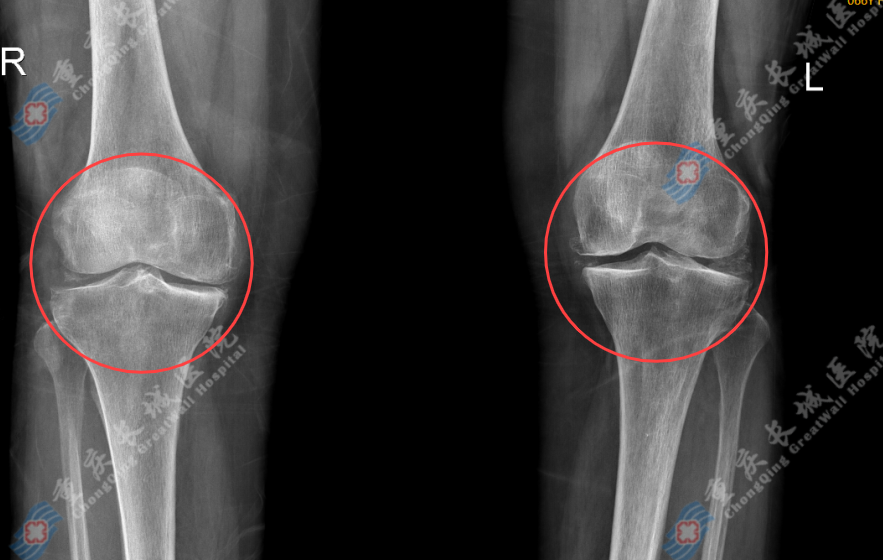

经检查,陈婆婆确诊为:双膝重度骨性关节炎、双膝关节囊积液。

骨性关节炎:膝关节炎主要指膝关节骨关节炎 (knee osteoarthritis, KOA)。该病是一种以膝关节软骨退行性病变和继发性骨质增生为特征的慢性关节疾病,膝关节炎症状往往进展缓慢,随着时间推移逐渐出现膝关节疼痛、肿胀、僵硬、畸形等,导致患者不能灵活活动,严重者可完全无法行动。